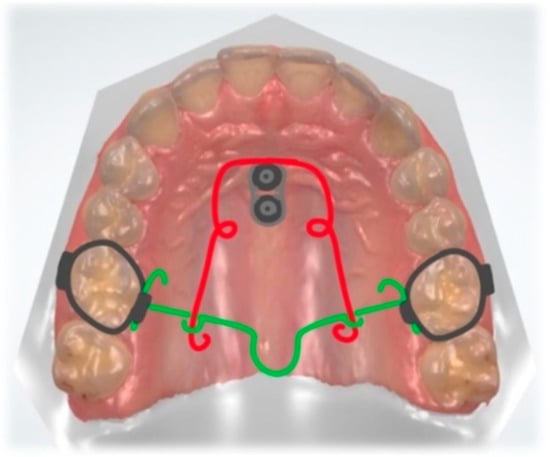

3.2. Palatal Impaction